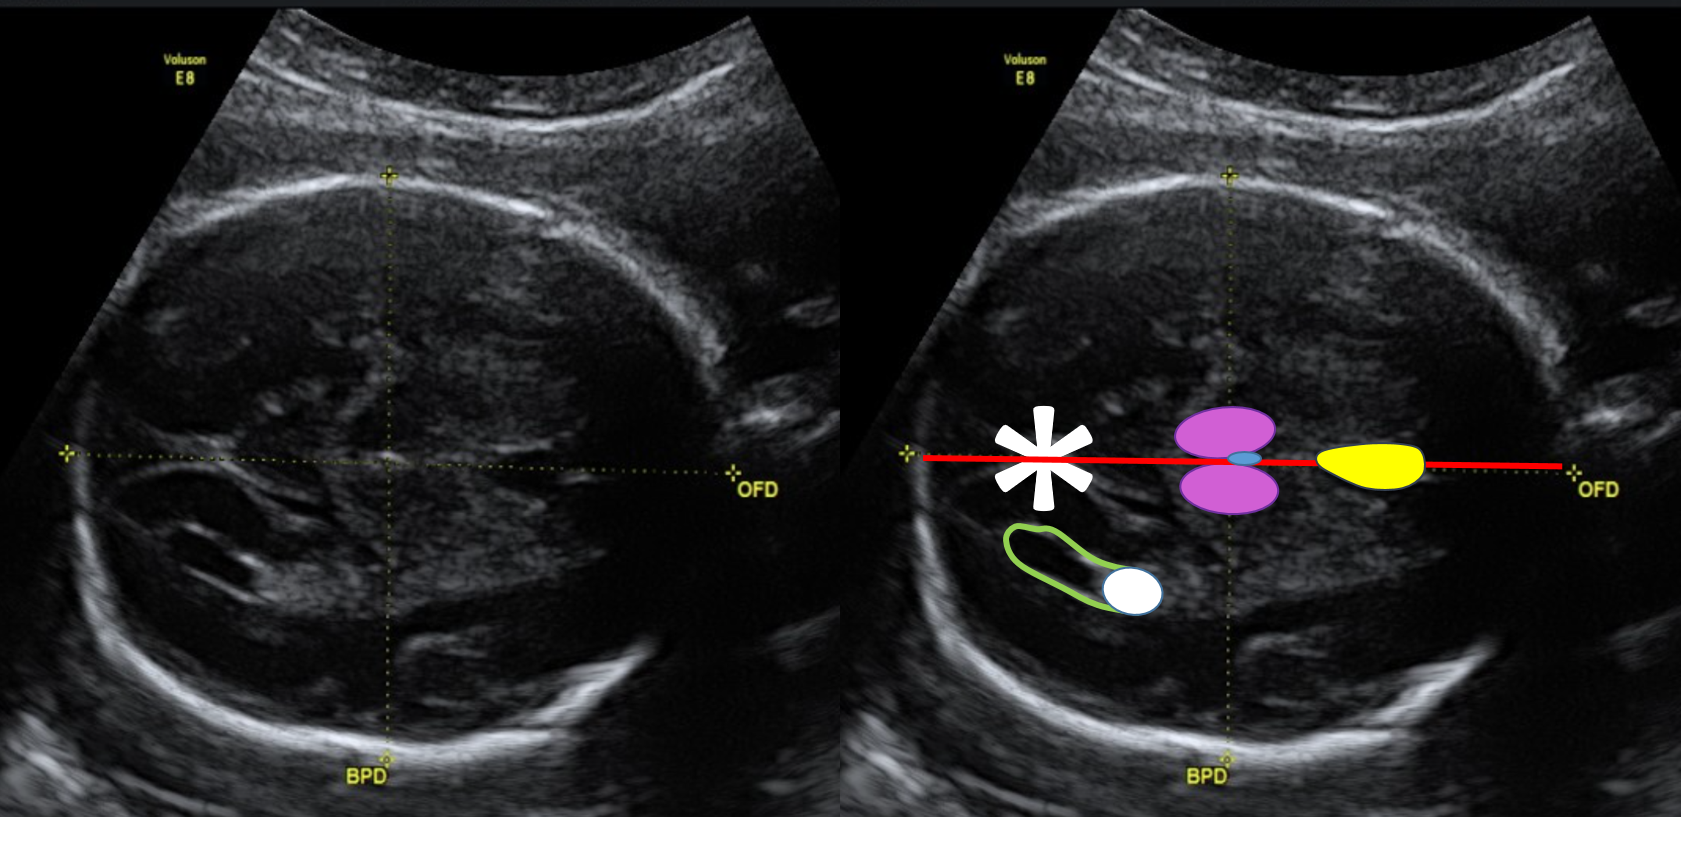

biometria overlay

Plano axial ideal para a medida da circunferência abdominal. Abdome com formato circular, obtido em corte transversal verdadeiro. O asterisco (*) indica o estômago. O contorno cinza delimita o corpo vertebral, posicionado às 3 horas. O contorno vermelho identifica a aorta descendente. O contorno amarelo evidencia a presença de apenas uma costela nesse plano. O contorno azul demonstra o seio portal,  correspondente ao segmento intra-hepático da veia umbilical, visualizado como um trajeto curto, lateral e aproximadamente horizontal, afastando-se da linha média para a direita do feto, em continuidade com o ramo esquerdo da veia porta, caracterizando o "sinal do taco de golfe". No plano adequado não são identificados rins, vesícula biliar, coração ou a inserção do cordão umbilical na parede abdominal.